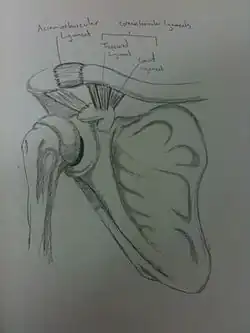

The acromion of the scapula is connected to the clavicle by the superior acromioclavicular ligament. The coracoclavicular ligaments connect the clavicle to the coracoid process. The two ligaments that form the coracoclavicular ligaments are the trapezoid and conoid ligaments. These three ligaments add support to the shoulder joint.

There are four types of soft tissue disruptions that may cause acromioclavicular separation:[8]

- The conoid and trapezoid ligaments may tear at any location

- The lateral clavicle may ride upward after being avulsed from its periosteum

- The acromioclavicular ligaments may be torn

- The conoid-trapezoid ligament origin may avulse from the coracoid